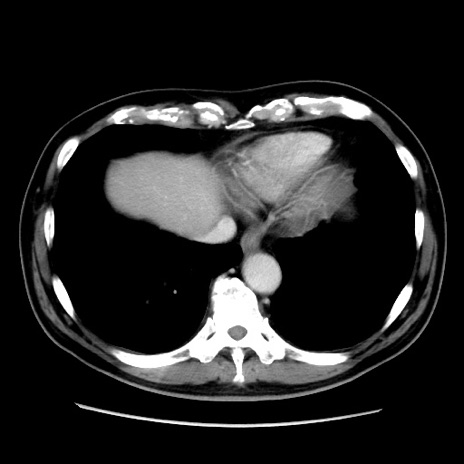

症例16(横断像)

【症例】 70歳代男性

【主訴】 腹痛、嘔吐

【現病歴】 約1ヶ月前より間欠的に腹痛と嘔吐あり、当院消化器内科を受診したところCTで多発する肝臓のLDAを指摘され、精査中であった。以降は消化器症状は安定していたが、2日前より嘔気と腹痛があり、同日より排便・排ガスが消失した。改善認めず、 本日、救急外来を受診した。

【既往歴】 大腸ポリープ切除後。

【身体所見】意識清明・会話良好、BT 36.3℃、BP 127/80mmHg、 P 80bpm、腹部:膨満あり、平坦・軟、上腹部正中および下腹部正中に圧痛あり、反跳痛なし、筋性防御なし。

【データ】WBC 7200、CRP 0.77